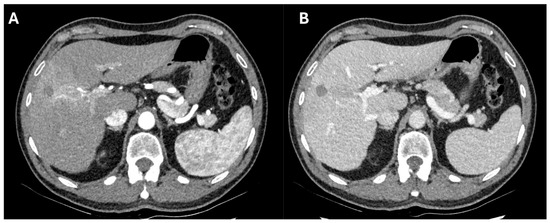

Figure 2. Computed tomography arterial (A) and portal (B) phase of a case of successful downstaging by a combination of loco-regional therapies and immunotherapy. After a microwave ablation of a Sg8 HCC, the patient developed a neoplastic thrombosis of Sg8 Glissonean pedicle. He was treated with trans-arterial radio-embolization followed by 20 cycles of Atezolizumab–Bevacizumab. After disappearance of contrast-enhancing tissue at the Sg8 pedicle and normalization of alpha-fetoprotein (from 42.9 to 8.1 ng/mL), the patient was waitlisted for liver transplantation 1 month after the last administration of immunotherapy. He was transplanted 10 days after and had an uneventful postoperative course, with no sign of acute rejection. At 5-month follow-up, he had normal liver function and no evidence of recurrence.